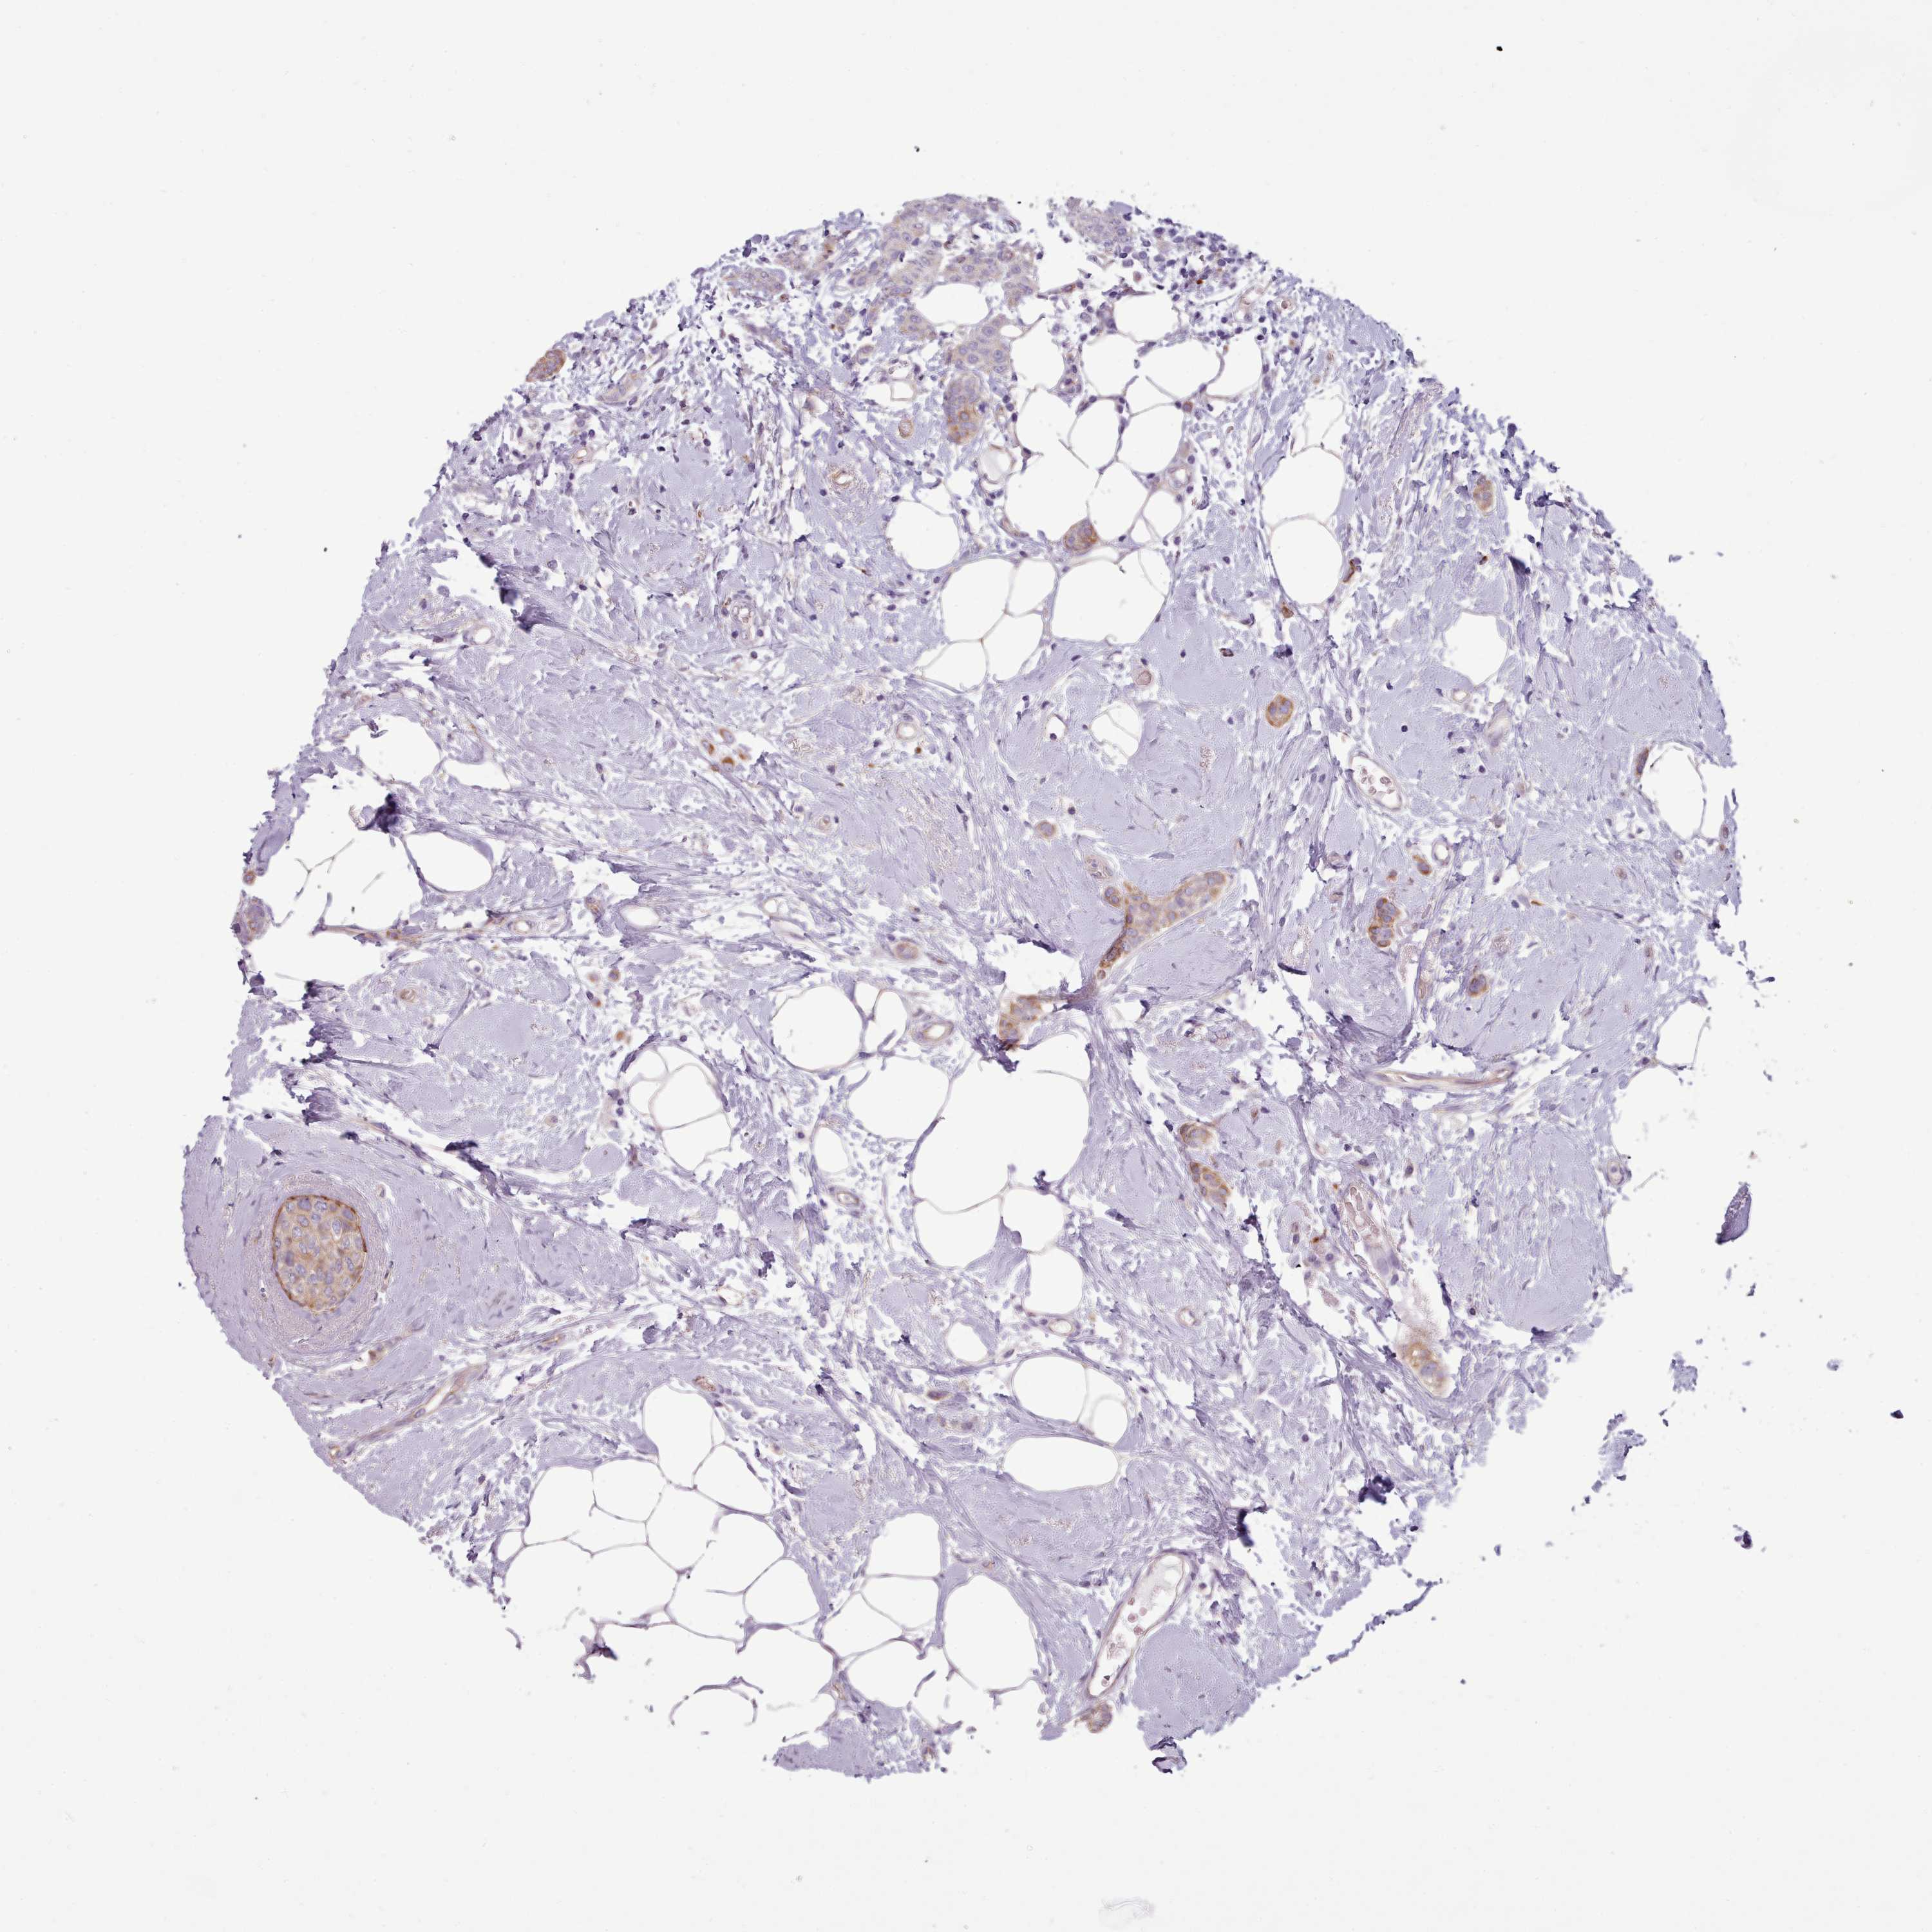

BRCA TCGA BRCA VALIDATION PROTEIN EXPRESSION

ANTIBODIES

AND

VALIDATION